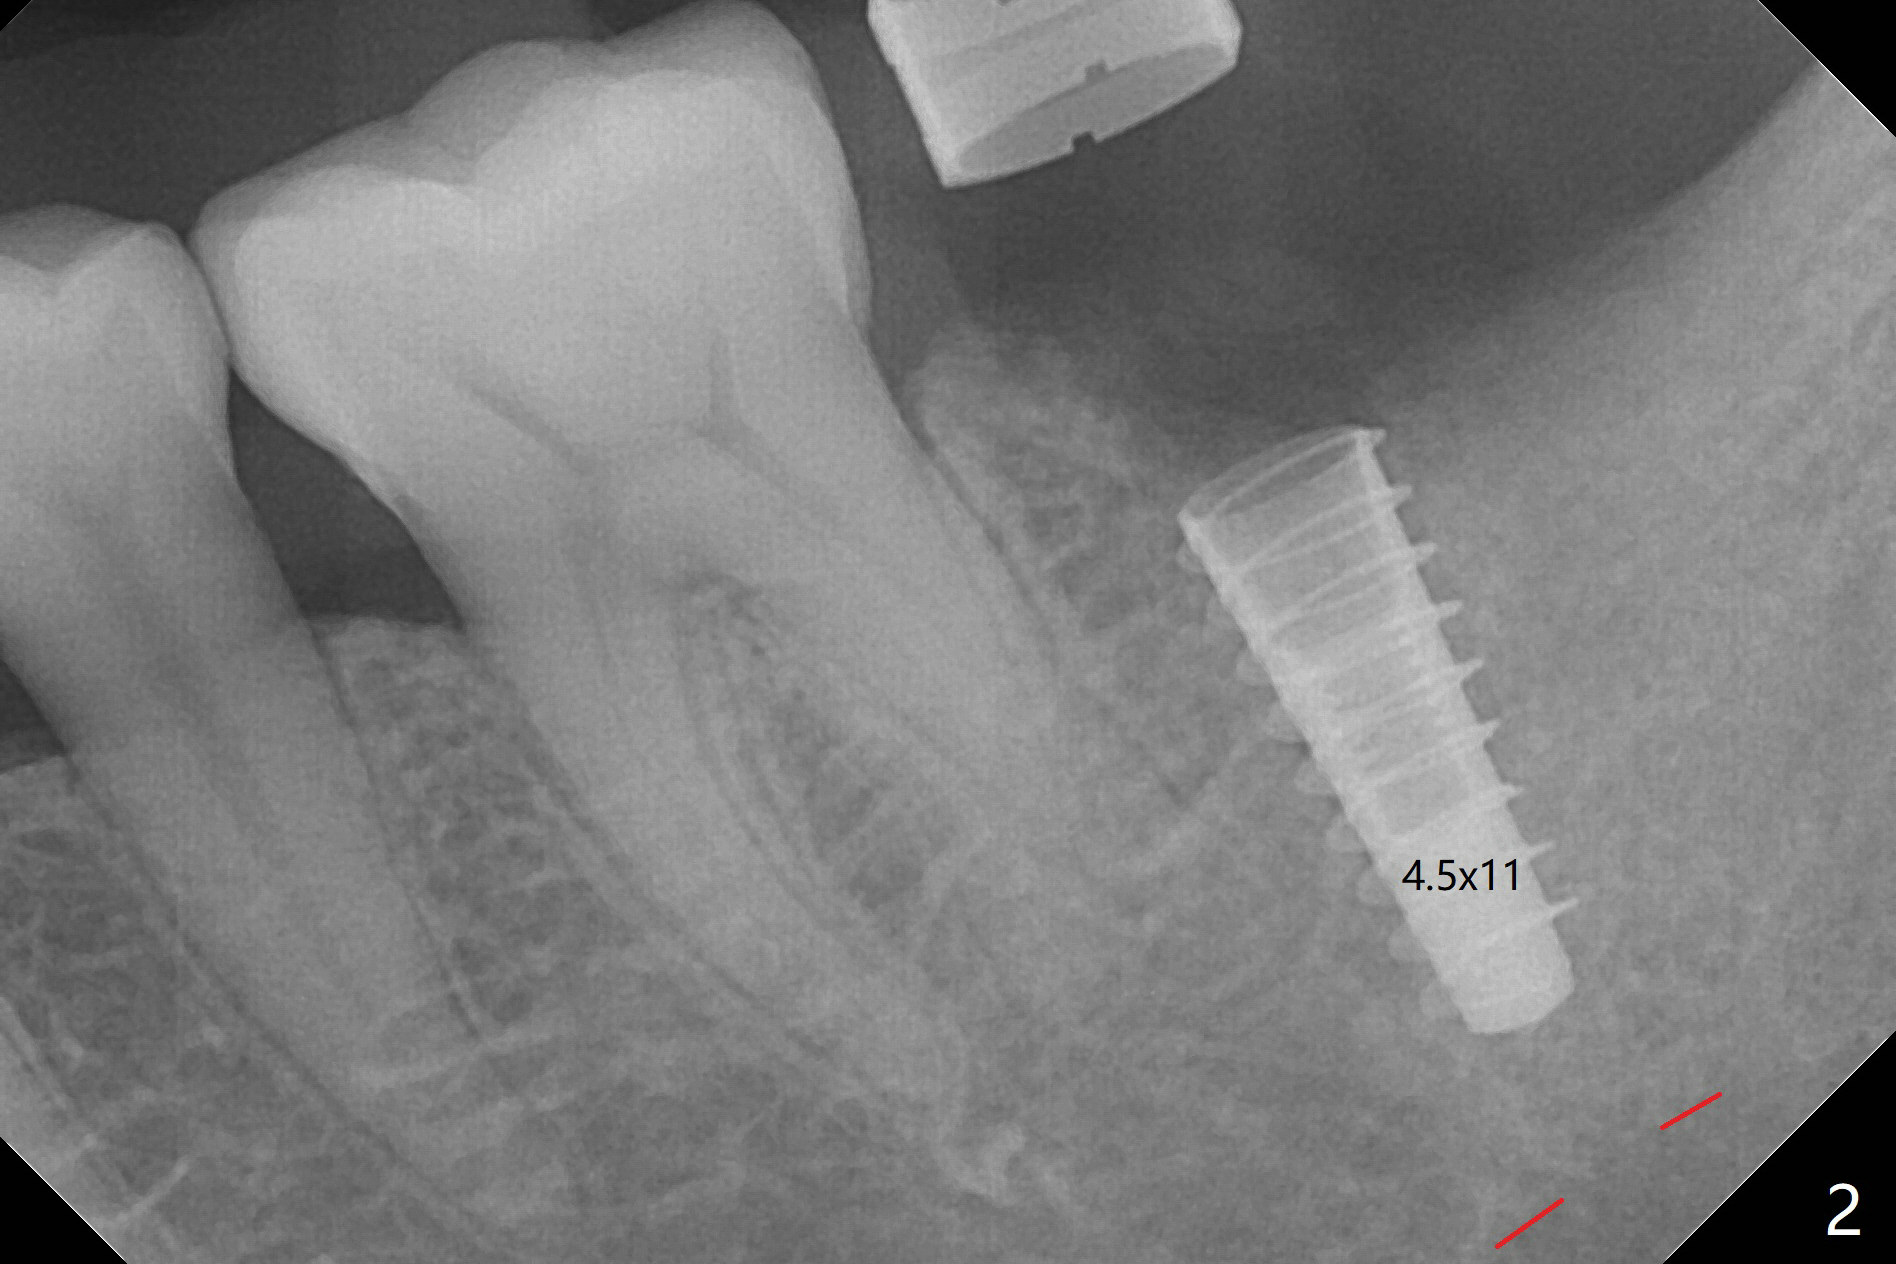

左下7钻洞中出现三种情况:容易出血(血小板减低(9万)),疼痛(根尖肉芽肿)和骨质疏松,钻洞深度还没达到,使用短小报废植体拍摄根尖片(图一),之后下颌牙槽神经阻断,钻洞没有疼痛,但是未注意骨质疏松问题,按照正常钻洞顺序,所以正式植体扭力低,10 Ncm(图二),放置骨粉和不可吸收膜,PTFE缝合(图三)。术后一周膜舌侧稍微外翻(剪太小些,图四)。病人将术后五周回来去除膜,之后拍摄咬翼片证实骨粉丧失与否。其实病人提前回来,抱怨缝线不适,膜不翼而飞(图五,折线后),患侧咀嚼,因为对侧下颌第二磨牙疼痛又不肯拔除。The bone graft placed at the time of immediate implant (Fig.3 *) is apparently changing into the normal bone 4 months postop before uncover (Fig.6). After removal of the bone coronal to the implant with a curette, a 4x4(3) mm pair abutment is placed (Fig.7). Two weeks later the abutment screw is torqued at 20 Ncm.